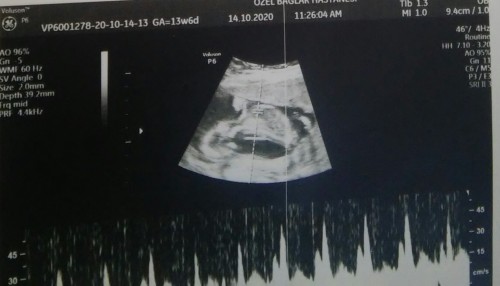

Lütfen anlayan varsa tahmin edebilir mi teşekkürler

Kız  gibi duruyor canım rabbim hayırlı evlat etsin inşallah ")

Erkek sanırım cnm.

Kız geçti içimden rabbim sana bağışlasın Amin

Bacak arası bu görüntü değil mi canım.

Ben kız gibi gördüm kuzum ya. Rabbim gönlüne göre versin.

Malesef bilemedin bacak arasi atmışim zoomlu pipi resmi

Doğrudur canım. Ben kıza benzetmiştim.

Ultrason resmine bakmadan ve anlamayan rica ediyorum tahminde bulunmayin

Sanki iki dudağı var gibi . Kız sanirsam

Bence erkek çıkıntı var çünkü kiz da bu kadar olmuyor dünde ben ogrendim aynı böyleydi :)